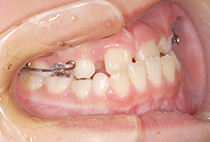

診断の結果は、以下が原因の骨格性反対咬合。

反対咬合でよくあるケースです。

治療方法は、小さな上顎の成長誘導。

急速拡大装置と前方けん引装置を使用します。

かみ合わせもお顔立ちも大きく改善。

その後も機能訓練×かみ合わせの維持をコツコツ継続。

成長のピークに合わせて上顎をもう一度拡大し、前歯のかみ合わせをさらに安定化。

成長期の波に合わせることで、より調和の取れた横顔へ。

治療開始から6年後。

治療終了後2年経っても、安定したかみ合わせと自然な横顔をキープ。

2年生で外科矯正と言われた受け口も、4年生になる頃にはすでに「バランスの良いお顔立ち」に。のびのびと成長期を過ごすことができました。